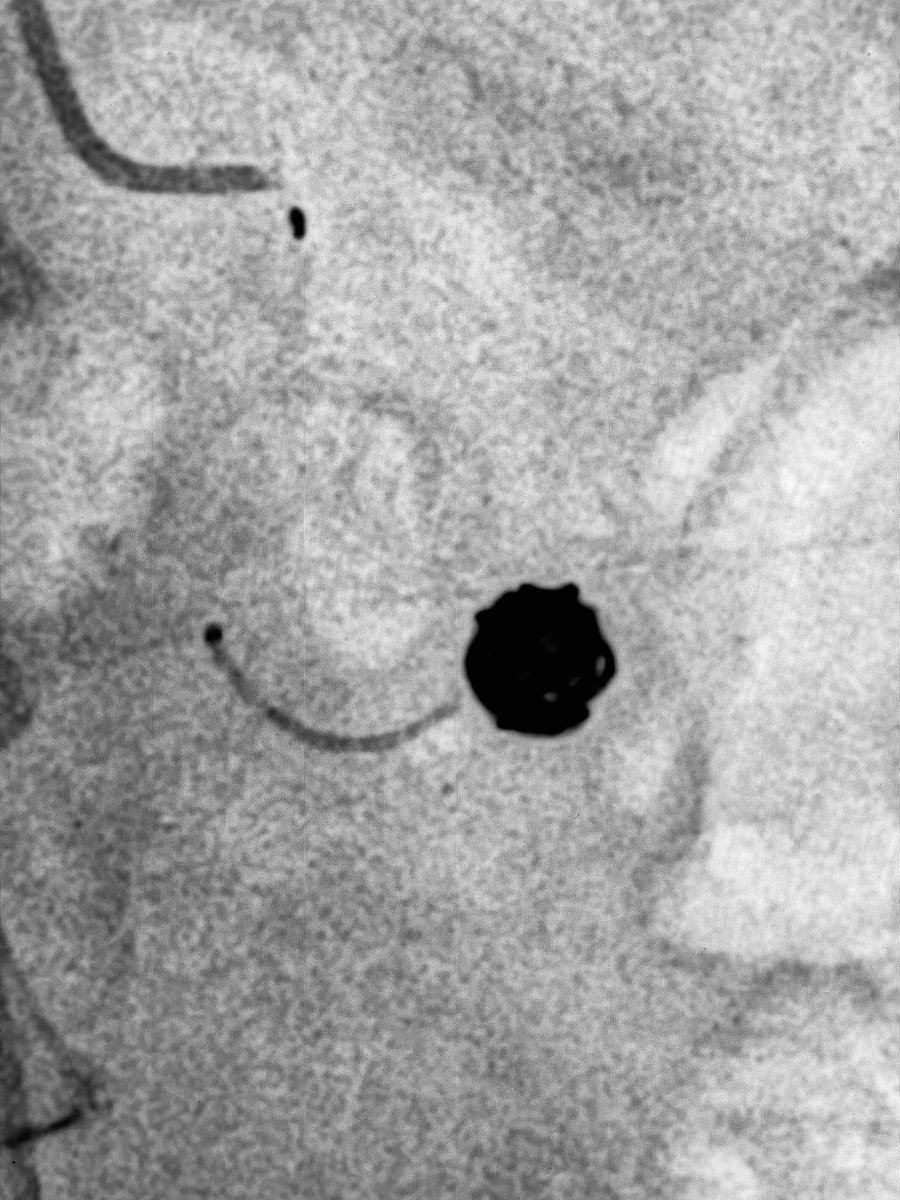

@DrShannonThomas @SIRRFS @SIR_ECS @VA_Int_Oncology @PenVascular Erased the original tweet by mistake. Inflammatory/ruptured SMA branch aneurysm and pain.

@DrShannonThomas @SIRRFS @SIR_ECS Correct! Coiled the aneurysm and the inflow/outflow with Penumbra Ruby, POD and Packing coils. @VA_Int_Oncology @VenuVadlamudiMD @PenVascular